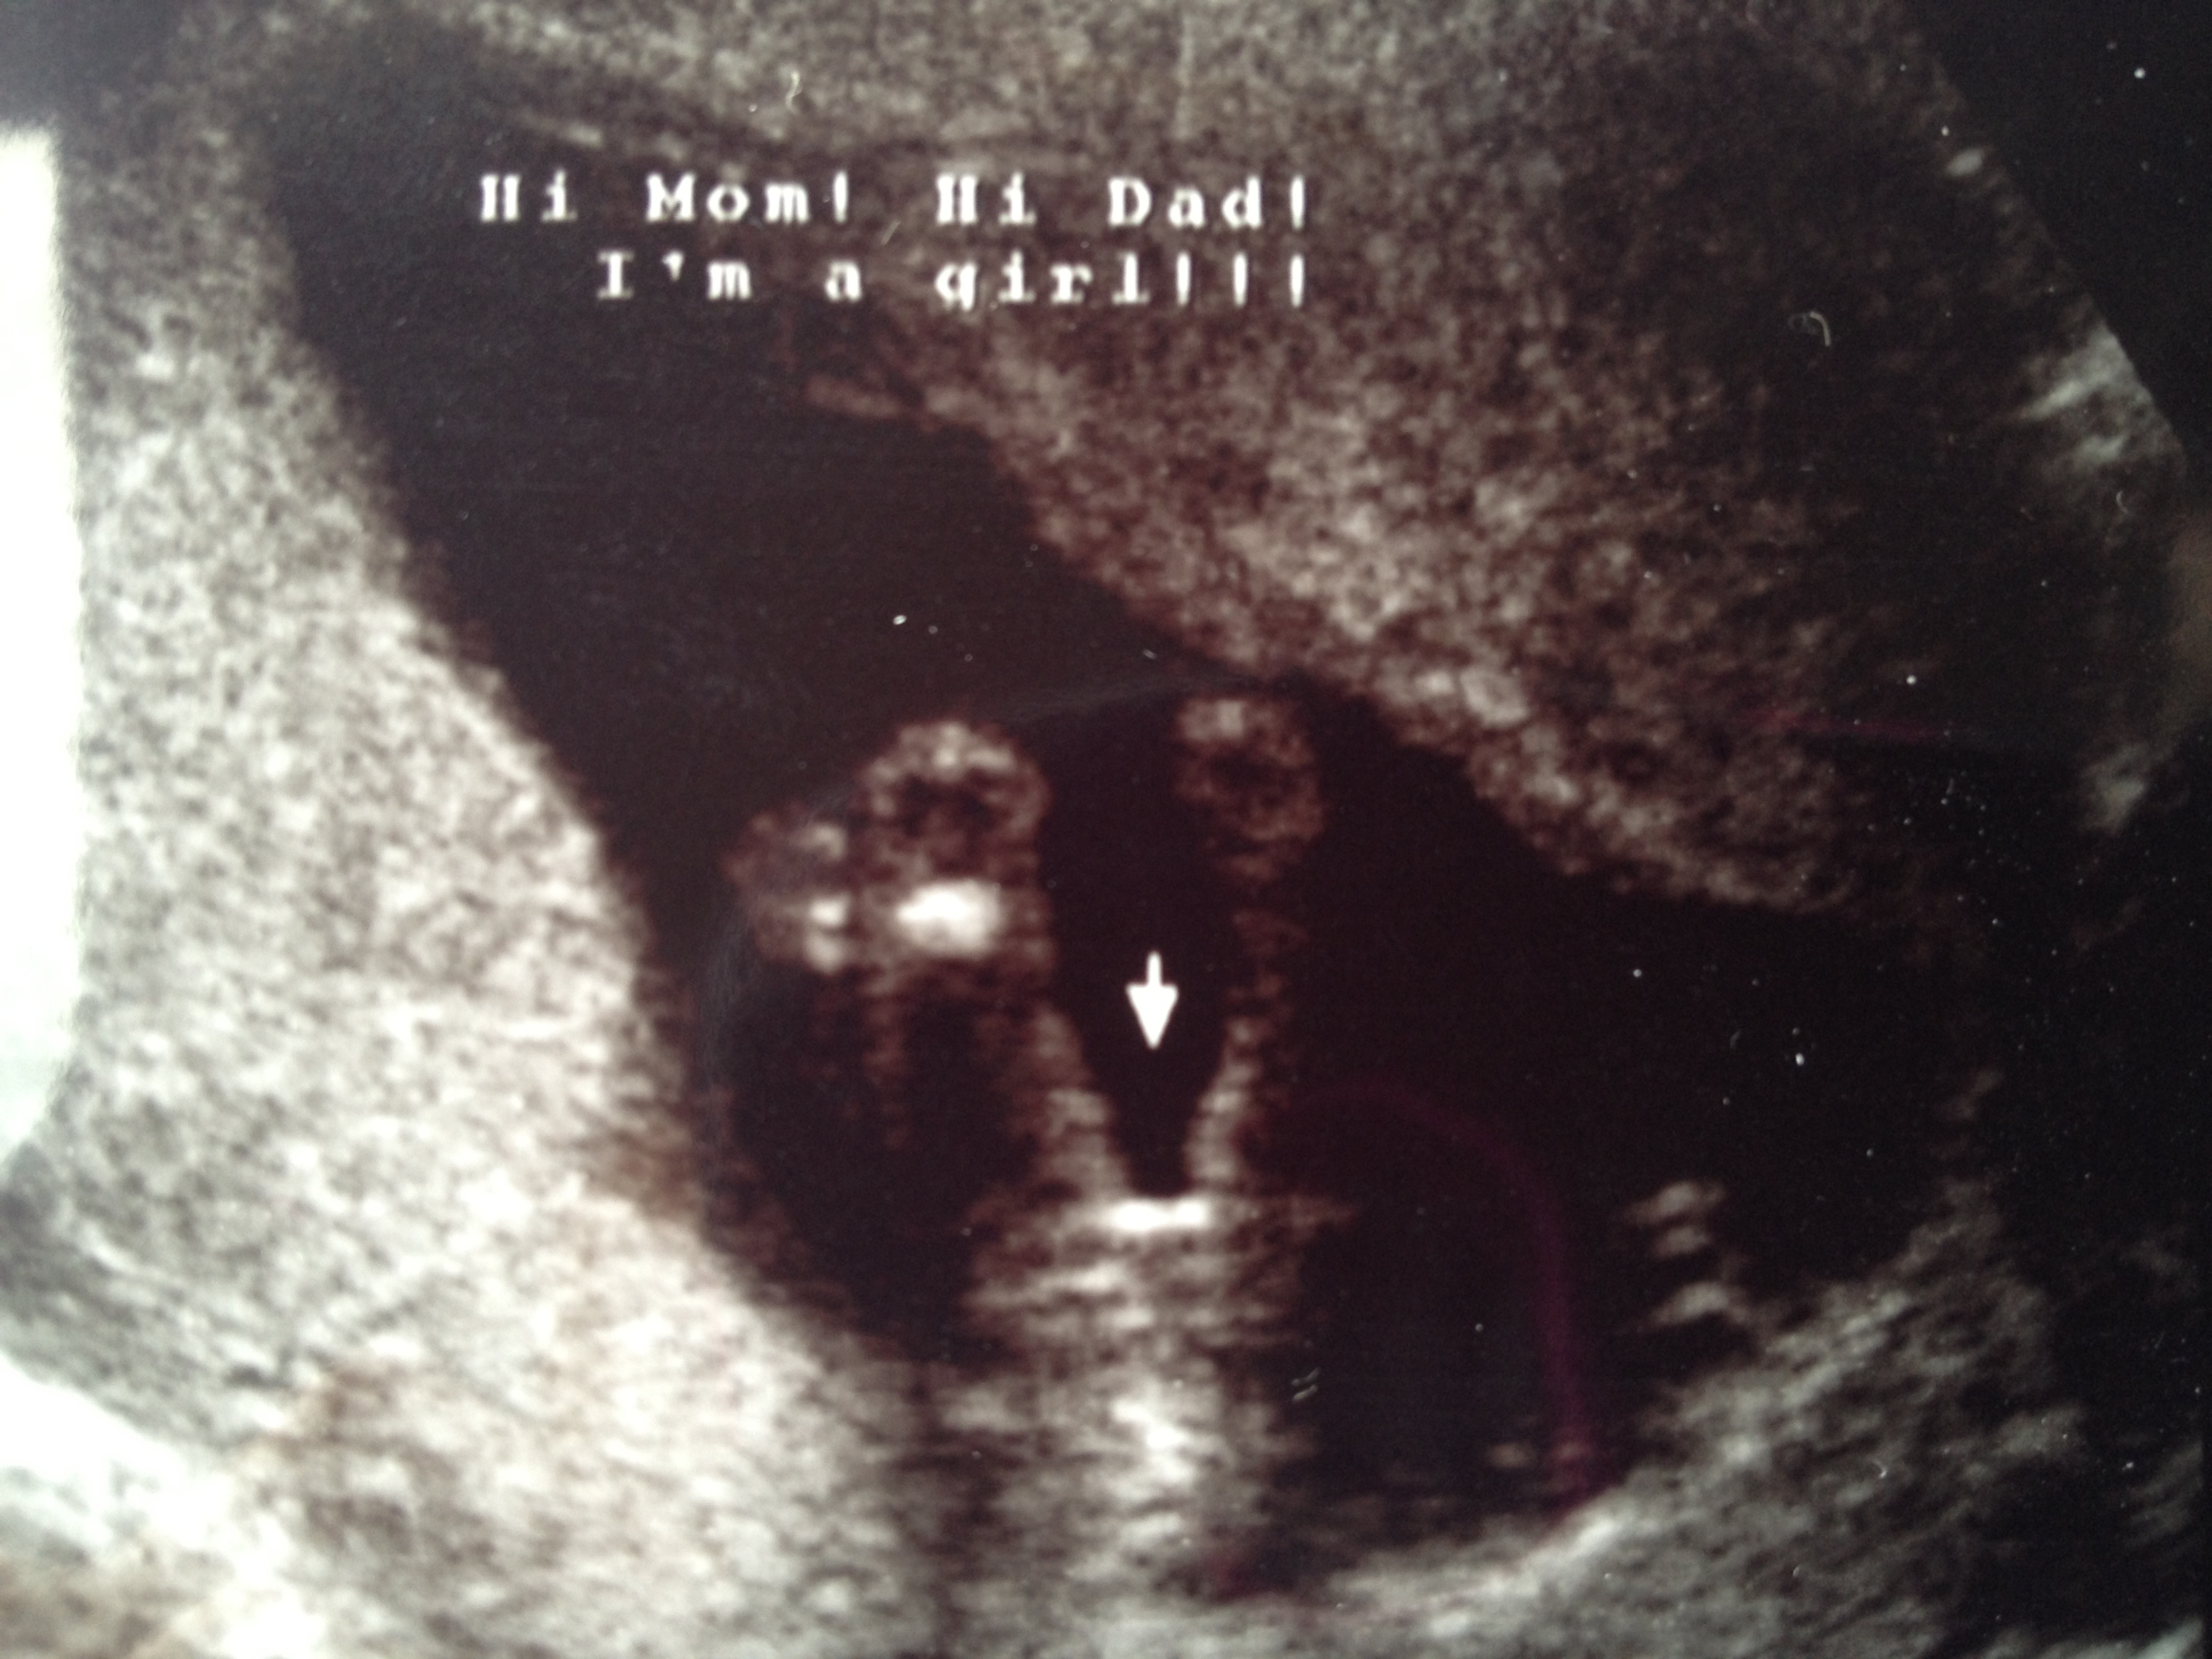

15 week ultrasound and it's a......